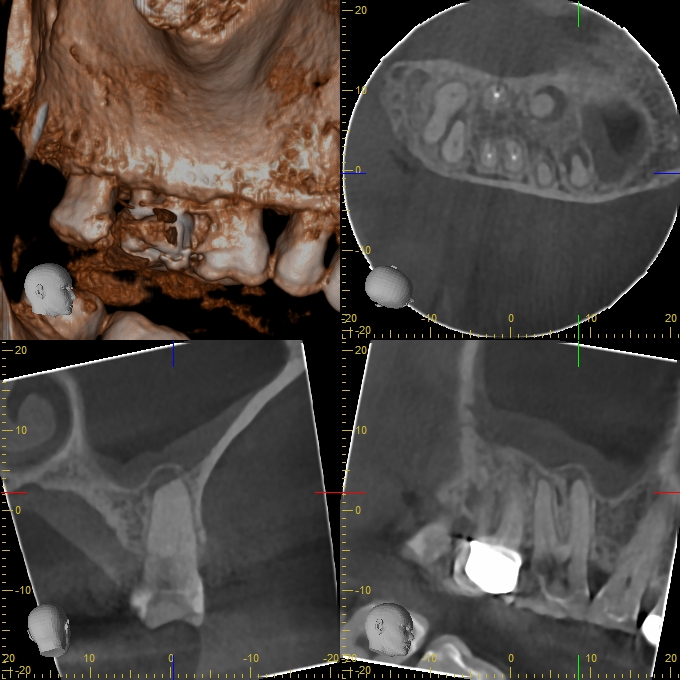

XYZView_20140429_111901

680 × 680

2D vs. 3D (XXVII)